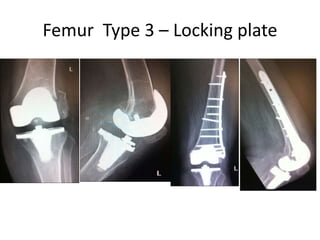

Femur Type 3 โ€“ Locking plate

Femur Type 3โ€“ Locking plate